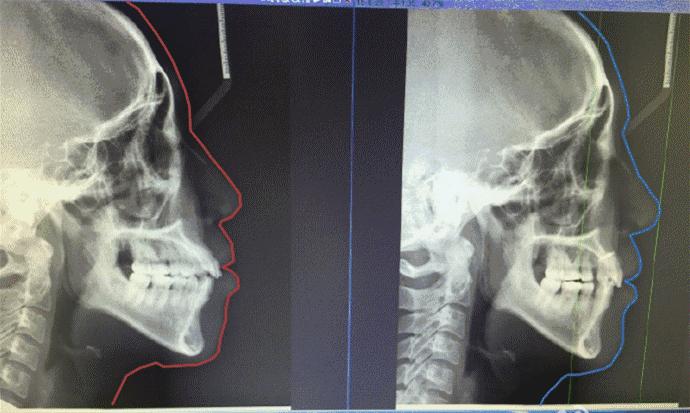

年龄:21岁

性别:女

牙齿情况:深覆盖深覆颌

矫正方式:自锁托槽矫正

矫治时间:2年8个月